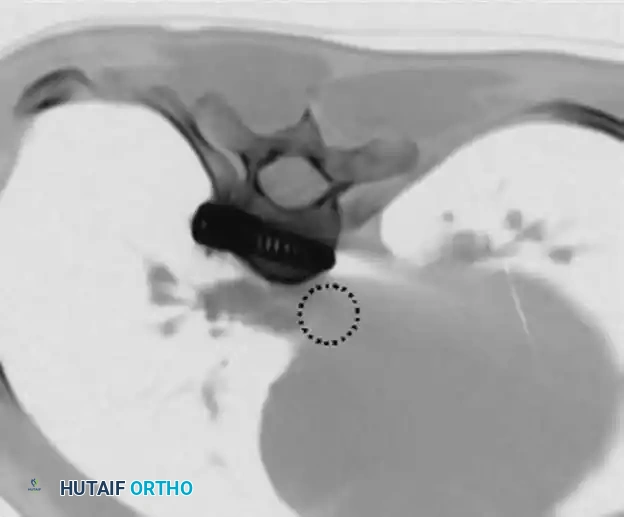

* Biomechanical Failures: Without meticulous attention to rod contouring and structural grafting, a kyphosing effect can occur, obliterating normal lumbar lordosis. Furthermore, because anterior screws rely on relatively cancellous vertebral body bone, proximal screw pullout or dislodgment is a known risk.

* Late Complications: Retroperitoneal fibrosis and vascular impingement from prominent instrumentation.

(CT imaging demonstrating the critical proximity of anterior thoracic screws to the descending aorta. Bicortical purchase must be executed with extreme caution.)